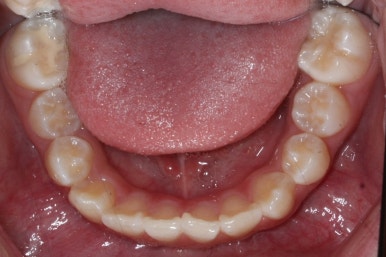

4개월이 지난 모습입니다.

송곳니가 덧니처럼 있었는데 아무것도 안해줬음에도 가지런한 느낌이 훨씬 좋아졌습니다.

공간이 생긴 송곳니는 편안한 위치로 좀 더 서서히 이동을 합니다.

4개월만에 유치가 빠지고 영구치가 조금씩 맹출이 되고 있는 것을 볼 수 있습니다.

8개월이 지난 모습입니다.

장치는 앞니 4개 + 헤드기어만 사실상 했습니다. 송곳니에는 아무것도 하지 않았죠.

덧니의 변화된 모습이 느껴지시나요?

다시 한 번 말씀드리면 공간확보만 된다면 서서히 좋아지게 됩니다. 100%는 아니기 때문에 추후에 전체적으로 정리를 해줄 필요가 있는데 미리 이렇게 해두면 훨씬 추후에 작업이 간소해지죠.